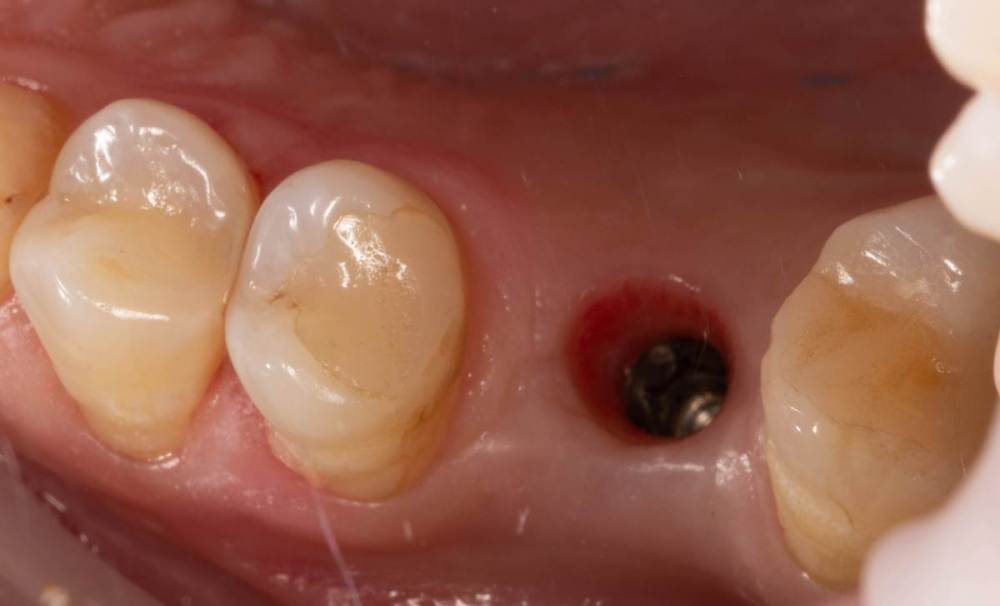

Женька Опубликовано 15 ноября, 2021 Автор Поделиться Опубликовано 15 ноября, 2021 Как и обещал... всего два фото... Когда-нибудь я буду всё успевать и делать нормальный интраоперационный фотопротокол) Ссылка на комментарий

Женька Опубликовано 19 ноября, 2021 Автор Поделиться Опубликовано 19 ноября, 2021 6 дней после... все разлетелось, еще и кровотечение на 5 день открылось, думается мне из-за швов. С нёба не снял ни одного шва. Первый раз такое, что через неделю в зоне имплантации швов почти не осталось у меня... при том, что натяжения не могло возникнуть ни откуда ведь (ну ок, отёк, но зона то маленькая). В прочем, контур слизистой вроде бы получилось восстановить. Уже думаю, а не купить ли вакуум формер и каппы делать, как Настя Смолякова. Ссылка на комментарий

Женька Опубликовано 10 мая, 2022 Автор Поделиться Опубликовано 10 мая, 2022 Раскрылся тут недавно. Контур естественно вогнутый был, не сработал мой сст (а если быть честным, то пожалуй умер). Снова решил попробовать ролл. Это сносный результат для этой техники? или есть "серьёзные" вопросы к её исполнению? 1 Ссылка на комментарий